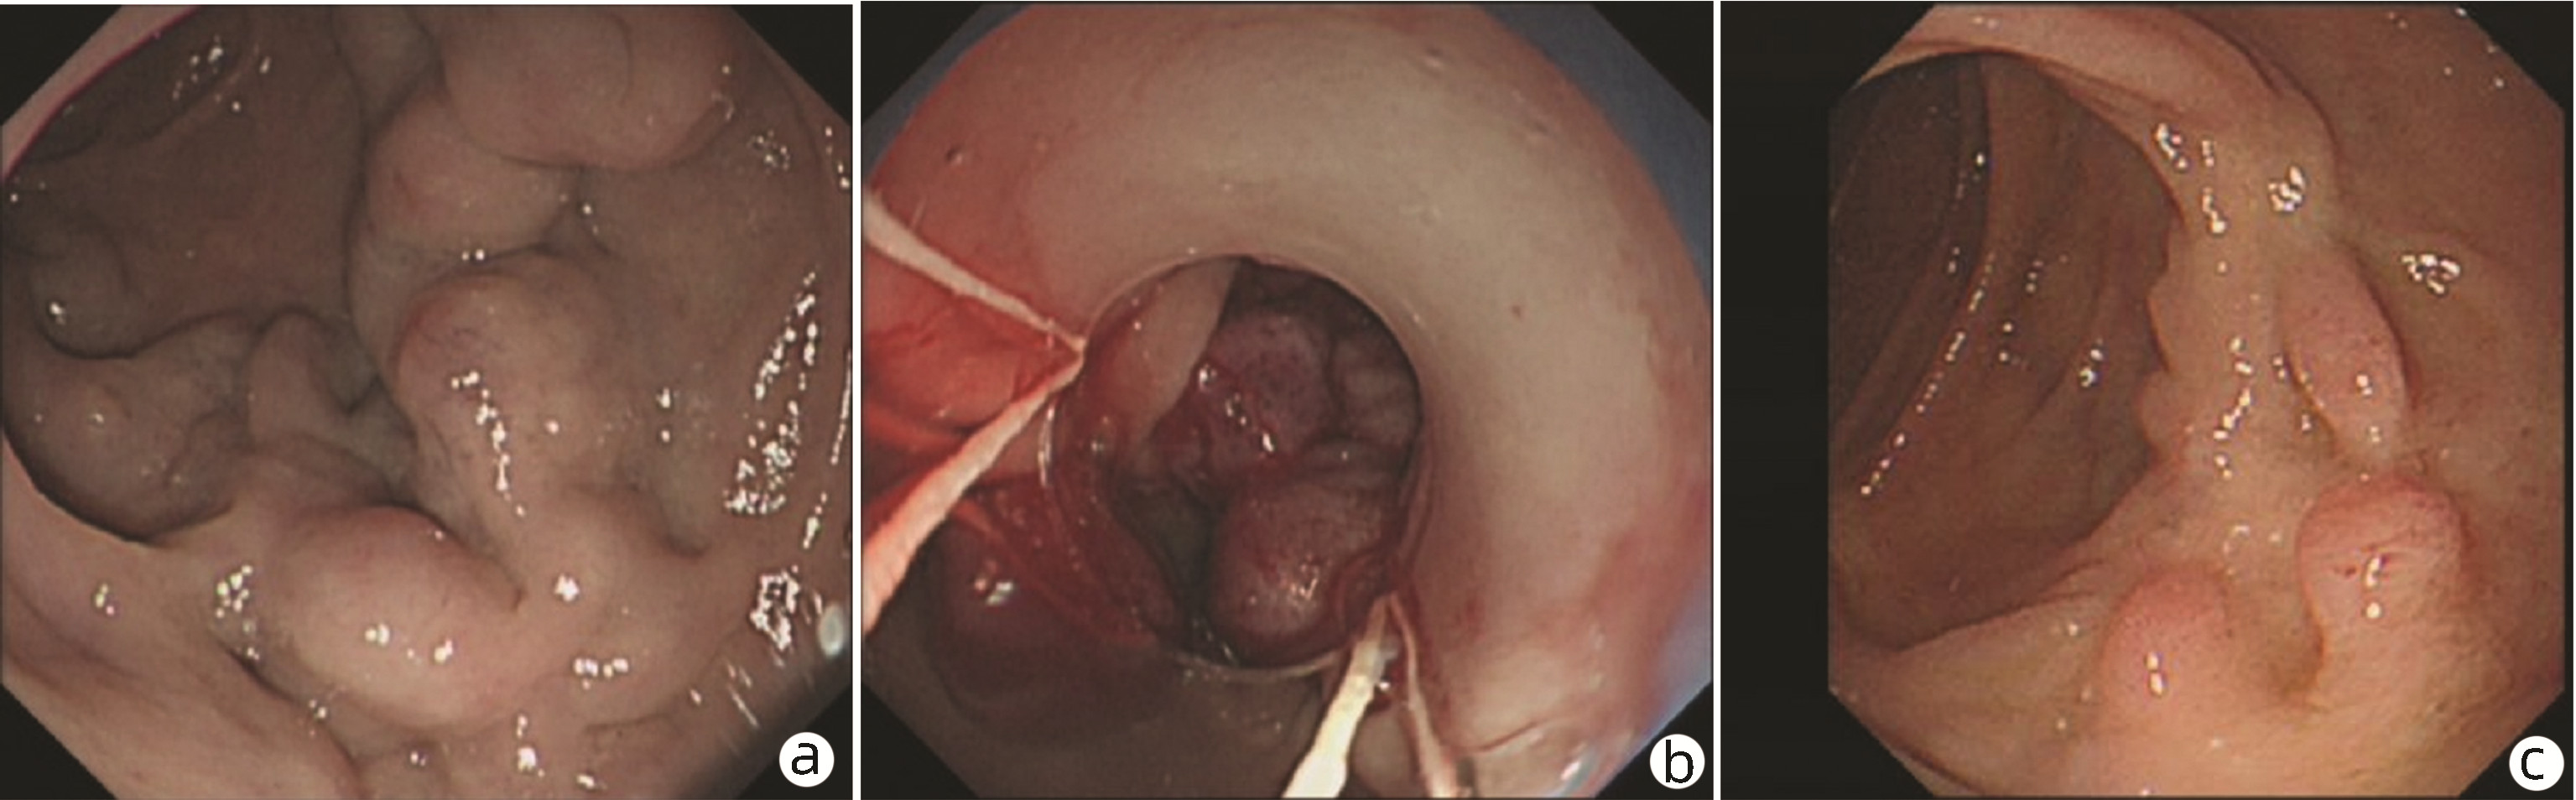

内镜下序贯套扎治疗食管胃伴十二指肠静脉曲张1例报告

文皓, 何朝晖, 蒋彤, 石国庆

2023, 39(3): 637-639. DOI: 10.3969/j.issn.1001-5256.2023.03.024

摘要(891) HTML (275) PDF (2676KB)(111)

摘要: